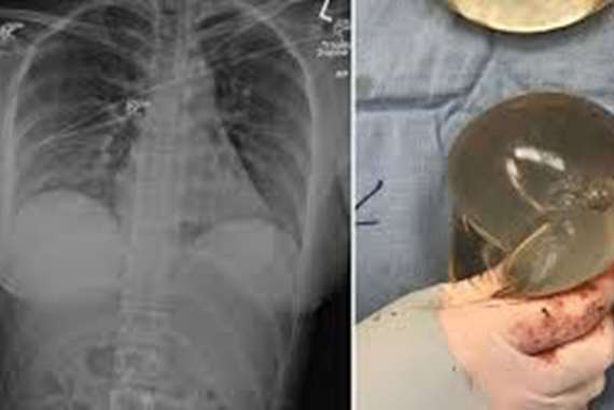

في واقعة غريبة ونادرة بكندا، أنقذت حشوة سيليكون، امرأة بعدما أصيبت برصاصة قاتلة في صدرها من مسافة قريبة أثناء سيرها في أحد الشوارع.

وكانت مجلة "سايج" الطبية،  قد كشفت في دراسة نشرت الأسبوع الماضي، والتي  تناولت حالة هذه المرأة، أن حشوة السيليكون في الثدي الأيسر للشابة البالغة من العمر 30 عاما، ساهمت في انحراف الرصاصة بعيدا عن أعضائها الحيوية.

وأضافت أن الحادثة وقعت في عام 2018، ولكنها تعتبر واحدة من عدد قليل من الحالات التي تم فيها إنقاذ امرأة عن طريق حشوات صدر.

وكانت  المريضة، التي لم يذكر اسمها، قد ذهبت إلى قسم الطوارئ في المدينة الكندية، بعد الشعور بالألم في صدرها ورؤيتها دماء.

واكتشف الجراحون جرحا واحدا وأزالوا رصاصة من تحت صدرها الأيمن.

وبحسب الدراسة فقد أزال الأطباء حشوة السيليكون وصوروها بهدف دراستها، وقد أظهرت الأشعة المقطعية أن الرصاصة مرت عبر الحشوة اليسرى وضربت اليمنى.

وفي تفاصيل الواقعة أيضا التي نشرتها الدراسة فإنه بناء على مسار دخول الرصاصة إكلينيكيا وتقويمها إشعاعيا، فإن المصدر الوحيد لانحراف الرصاصة هو حشوة الثدي الأيسر.